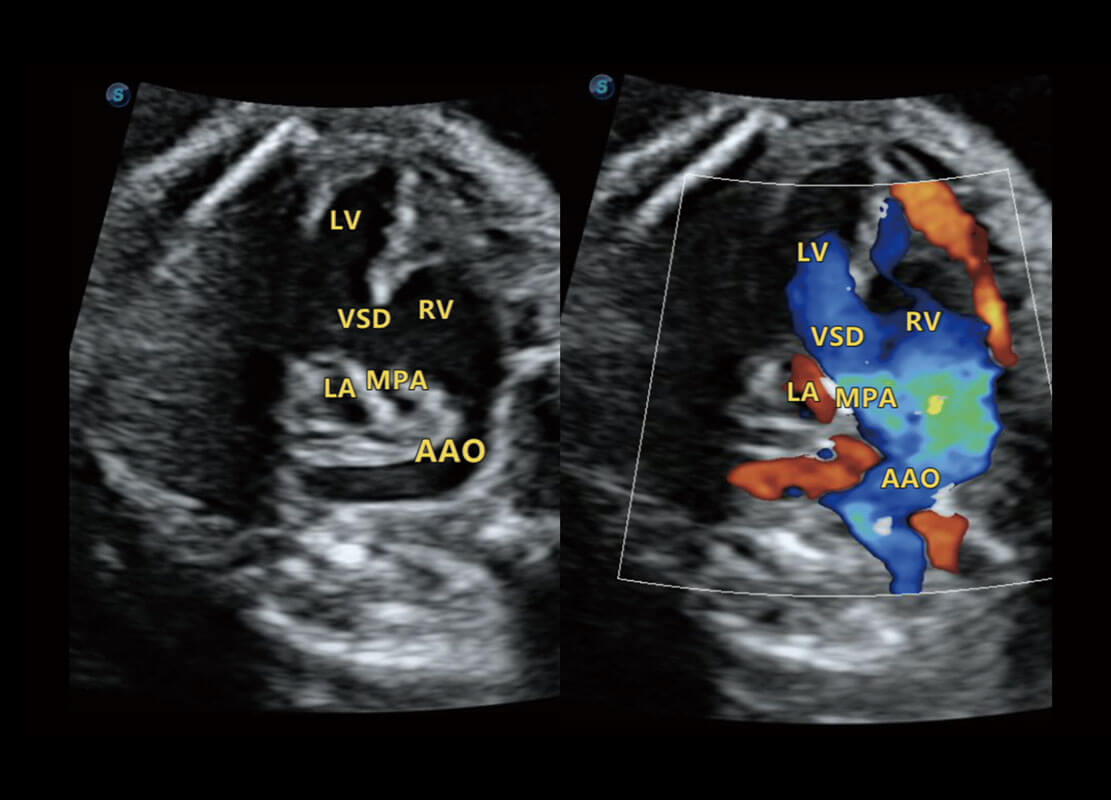

P60搭载一系列胎儿心脏成像技术,实现精细的胎儿心脏评估。

四腔心血流

右室双出口

胎心容积成像